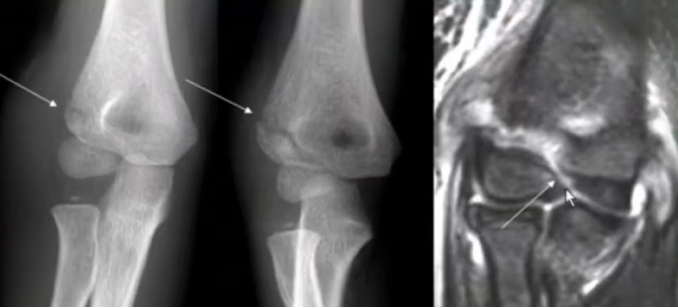

MRI和超声可评估软骨完整性。MRI因需镇静且费用较高,通常不作为常规首选。有许多文献报道在术中使用超声来更好地评估肱骨远端的关节面,但这种方法的确切作用目前也尚不统一。

图9A 右肘关节前后位(正位)X 线片:显示外侧皮质 3 期骨折,外侧间隙极小,移位≤2 mm。B 内斜位 X 线片:显示骨折线贯穿肱骨外髁,延伸入关节内,骨折间隙外侧与内侧宽度一致。C 短 T1 加权反转恢复(STIR)磁共振成像:显示软骨完全断裂。

肘关节造影:评估关节面复位的重要手段,取0.5~1.0ml造影剂稀释后注射,剂量超3~5ml影响显影质量。常用于闭合复位手术中,辅助判断复位。